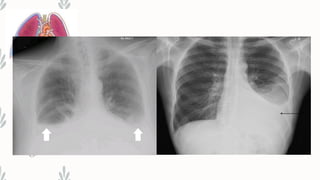

– Radiological examination:

– • X-ray chest PA view done in erect position-a total of 300mL of fluid is

needed to diagnose pleural effusion clinically and radio logically

– • Even 50mL of fluid can be demonstrated radio logically in lateral decubitus

Findings

– • Obliteration of cardio phrenic and cost phrenic angles

– • Loculated effusions

– • Lateral decubitus on side of effusion will show a shift in the

fluid level

• Tracheal and mediastinal shifts are seen in massive effusion